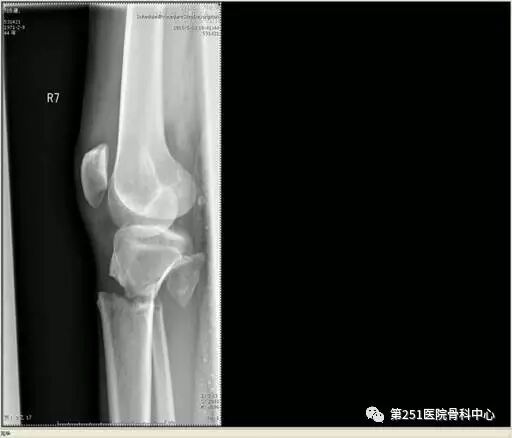

病例1:男性,40岁,车祸伤,胫腓骨多段骨折。

![]()